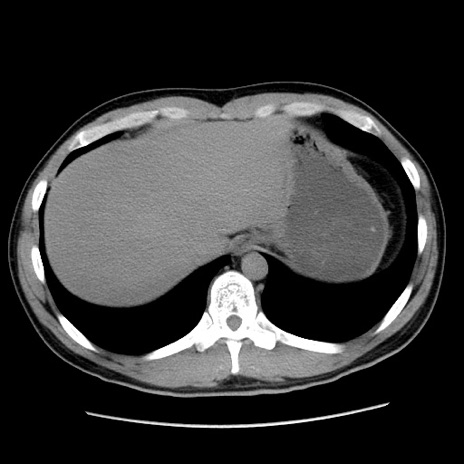

症例36(横断像)

【症例】20歳代 男性

【主訴】心窩部痛

【現病歴】今朝より上腹部痛あり。一旦軽快していたが再度出現したため救急要請。昨日夕に白身の魚を含む刺身を食べた。

【身体所見】BP 136/89mmHg、HR 74/min、BT 37.0℃、腹部:膨満、軟、心窩部に圧痛あり。反跳痛なし、筋性防御なし、腸雑音やや亢進あり。

【データ】WBC 17700、CRP 0.48